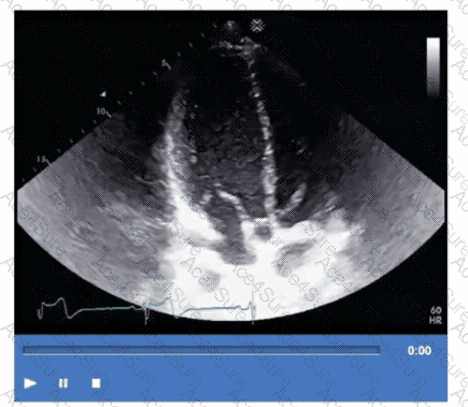

The echocardiographic image/video shows decreased brightness and penetration in the near field, making the anterior cardiac structures poorly visualized while deeper structures appear brighter. This indicates under-gain in the near field.

Increasing the time gain compensation (TGC) in the near field enhances the signal strength of superficial structures without affecting deeper tissues. This adjustment improves image quality by balancing the brightness across the field.

Increasing compression or decreasing overall gain would reduce the signal globally and are not specific for near field optimization. Decreasing TGC in the far field would reduce brightness deeper but does not address near-field issues.